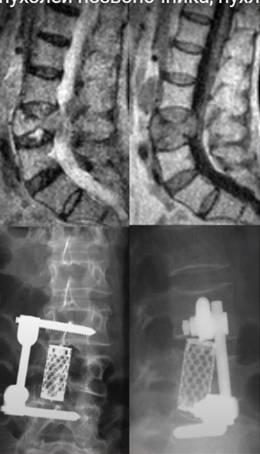

Хірургічне видалення пухлини хребта

При наявності показань, проводиться операція відкритого мікрохірургічного видалення пухлини хребта. Операція проводиться за принципами онко-хірургії з максимально можливою резекцією ураженої ділянки кістки до «здорової тканини» з усуненням компресії нервових структур. Після великих операцій з видаленням цілих хребців, проводиться установка спеціальних імплантів і протезів, для фіксації нестабільного хребетного сегмента.

Радикальність проведеної операції визначається гістологічною структурою пухлини, залученням до процесу спинного мозку і корінців.

При доброякісних пухлинах хребта, після тотального видалення пухлини в більшості випадків можна добитися повного видужання.

При злоякісних пухлинах хребта радикальну операцію навіть на сучасному етапі розвитку нейрохірургії досягти складно. Але і в цих випадках хірургічне видалення пухлини хребта значно зменшує больовий синдром, покращує функцію спинного мозку, який був здавлений пухлиною, подовжує період щодо благополучного стану пацієнта з задовільною якістю життя на місяці і роки (в залежності від ступеня злоякісності пухлини).